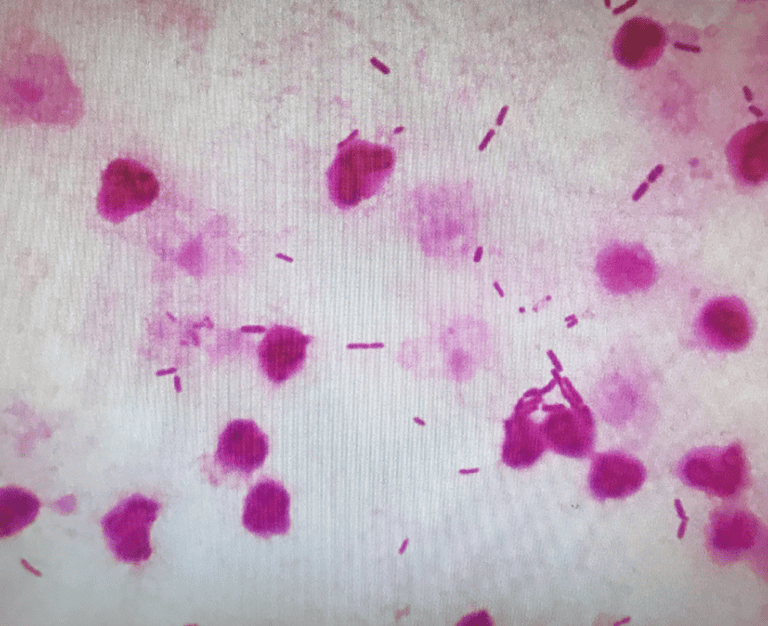

喀痰や尿などを直接スライドガラスに塗り、染色をした後顕微鏡で観察します。

※写真は尿検体です。染色をして 白血球や菌を見つけます。

丸い細胞が白血球で、棒状に見えるものは大腸菌です。